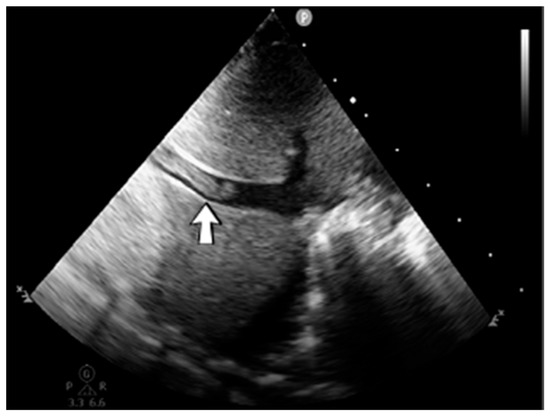

4.36. Case No. 36—Postnatal Intracardiac Thrombosis

A 7-week-old male infant (36 weeks, 2.50 kg), the first twin from a twin pregnancy, presented with a complex congenital cardiac malformation for an elective surgical procedure (Blalock–Taussig shunt). Heparin infusion for the shunt was started immediately after the intervention and anticoagulation was continued with enoxaparin due to good clinical condition. Then, 18 days after the procedure, a routine cardiovascular ultrasound revealed a thrombus in the left ventricle (Figure 16). The laboratory studies showed leukocytosis, highly elevated c-reactive protein, and modified coagulation tests (due to anticoagulant treatment). Continuous heparin infusion was reinitiated, but multiple intracardiac thrombi were detected during the following days. Treatment with alteplase was also started, but the patient’s condition continued deteriorating, leading to a negative outcome due to cardiac failure.

Figure 16.

Intracardiac thrombosis identified on cardiac ultrasound: left atrium and ventricle (A), left ventricle (B), apex (C).

Genetic testing confirmed inherited thrombophilia, with positive PAI-1 4G/5G promoter, MTHFR A1298C homozygous gene mutations, and Antithrombin and Protein C deficiencies. There was no known family history of thrombophilia. The mother had a previous therapeutic abortion due to a prenatal diagnosis of a complex congenital cardiac malformation.